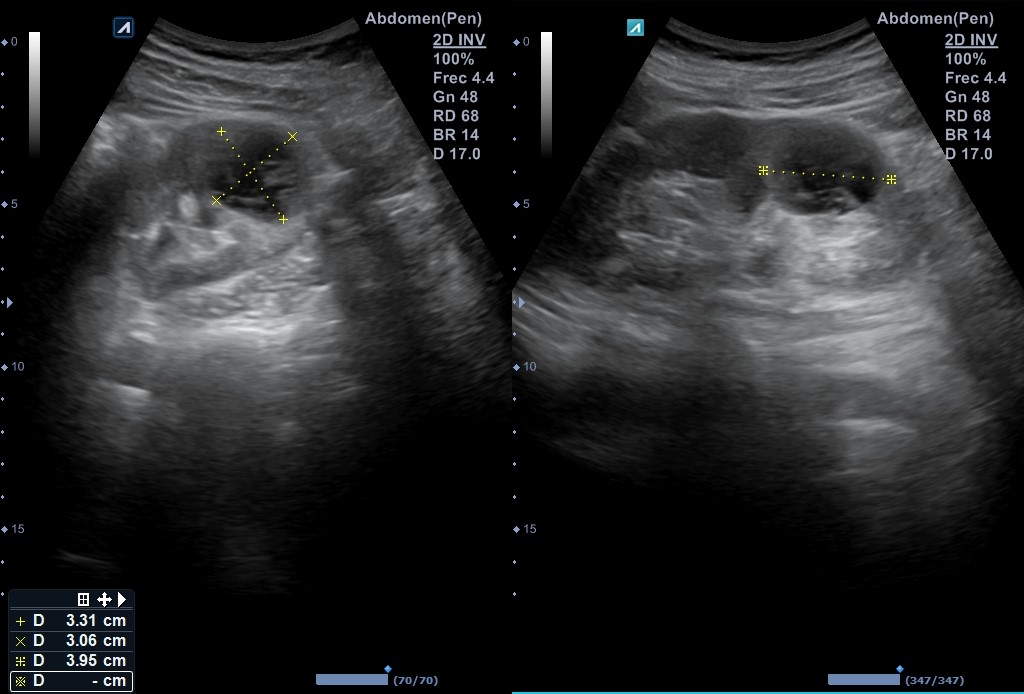

Ecografía vía urinaria: se evidencia una lesión en el tercio inferior de riñón izquierdo de aspecto quístico multiseptada, con polo sólido compatible con quiste Bosniak 3 de 30 x 29 mm que no capta Doppler, compatible en este contexto con absceso renal o neoformación renal. No otras alteraciones en resto del tracto urinario.